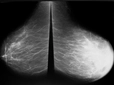

Tanı ve Teşhis YöntemleriKistik lezyonların tanısı, çeşitli görüntüleme yöntemleri ile konulmaktadır: